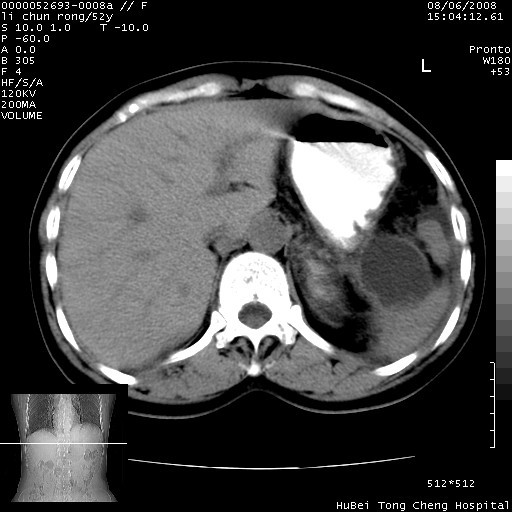

以下是引用云翔在2008-8-7 6:20:00的发言:[br]胰尾部囊性病变,考虑假囊肿,结合实验室检查疾病史

以下是引用zjzjr在2008-8-7 8:38:00的发言:[br]支持胰腺炎伴假囊肿形成,左肾小囊肿.少量腹水.

以下是引用随光逐影在2008-8-7 9:12:00的发言:[br]1)考虑胰腺炎伴假性囊肿形成可能性大;胰腺囊腺瘤待排。2)左肾小囊肿。3)少量腹水。